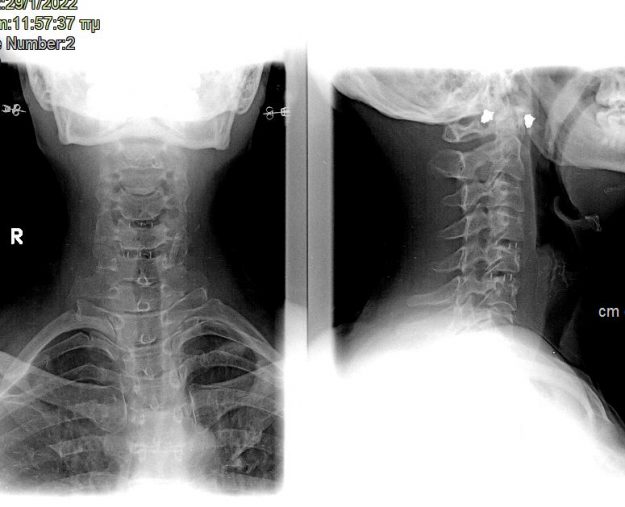

Νεαρή ασθενής 17 ετών με εκτεταμένη συριγγομυελία από την αυχενοπρομηκική συμβολή έως το τελικό τμήμα του νωτιαίου μυελού, λόγω συνδρόμου Chiari. Κλινικά αιμωδίες (μουδιάσματα) άνω άκρων, ζάλη. Αφού ο εργαστηριακός έλεγχος απέκλεισε συνοδά προβλήματα (πχ καθηλωμένο τελικό νημάτιο κ.α.) αποφασίστηκε η επέμβαση αποσυμφόρησης του οπισθίου κρανιακού βόθρου με ανάδυση των αμυγδαλών της παρεγκεφαλίδας και μηνιγγοπλαστική.…